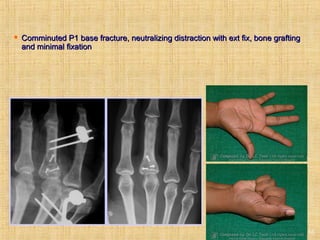

Treatment options (comminution)

Ext fix assist, bone grafting and minimal

internal fixation

 Comminuted P1 base fracture, neutralizingComminuted P1 base fracture, neutralizing

distraction with ext fix, bone grafting and minimaldistraction with ext fix, bone grafting and minimal

fixationfixation